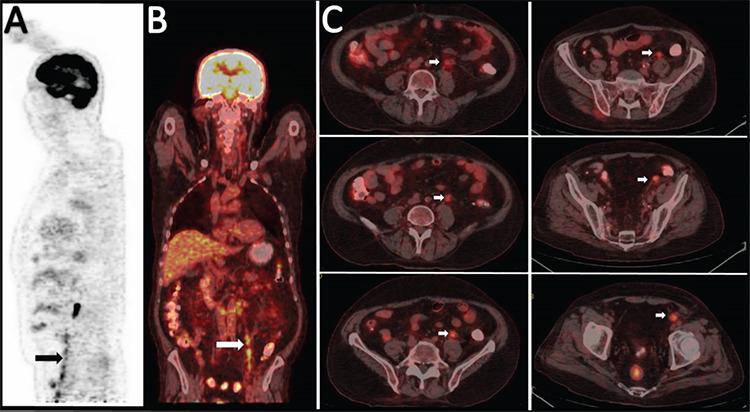

Myeloid Sarcoma Involving the Testicular Vein.

https://cdn.ncbi.nlm.nih.gov/pmc/blobs/b7ae/8386309/f7bb87500f49/TJH-38-224-g1.jpg